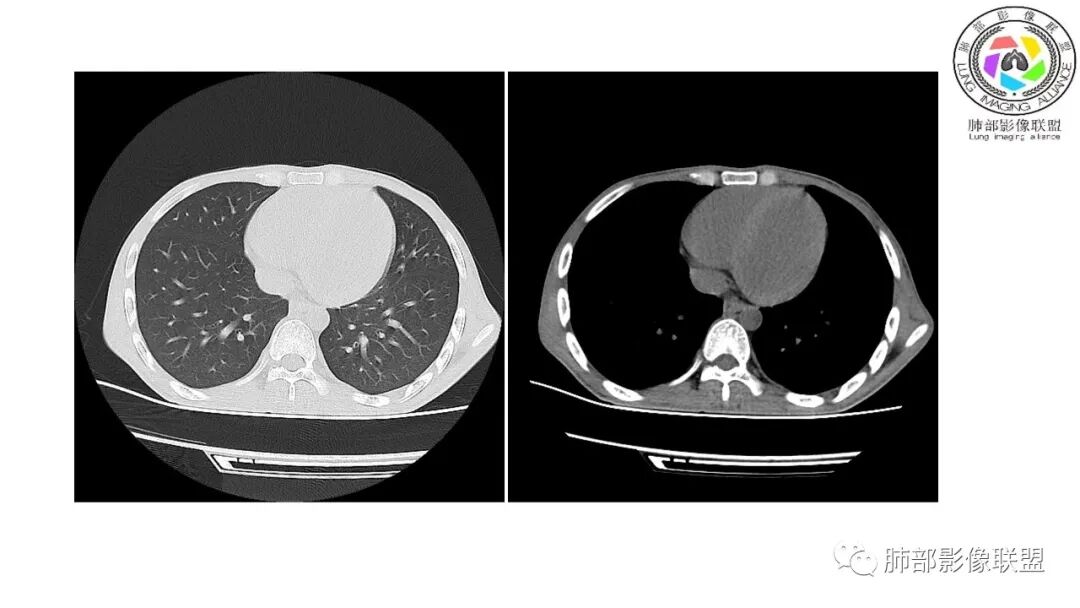

影像与临床:1.青年男性,HlV阳性,颜面部皮疹(未提供皮疹图像)、发热(高热),实验室CRP、PCT高,T-Spot阴性。2.右肺下叶空洞结节,壁厚不均,边界清楚,其内线状影,未见液平及钙化,未见卫星灶,纵隔淋巴结增大,双侧腋窝见增大淋巴结。心腔内低密度提示贫血可能。肝脾影增大,未见结节影及块影。腹膜后见多发增大淋巴结。

综合分析:本例肺部影像学改变并不具有特征性,空洞性病灶须与多种疾病鉴别,但年轻HIV阳性患者,高热,皮疹,肝脾增大,纵隔、腋窝、腹膜后见多发增大淋巴结等都强烈提示马尔尼菲篮状菌感染的可能性。